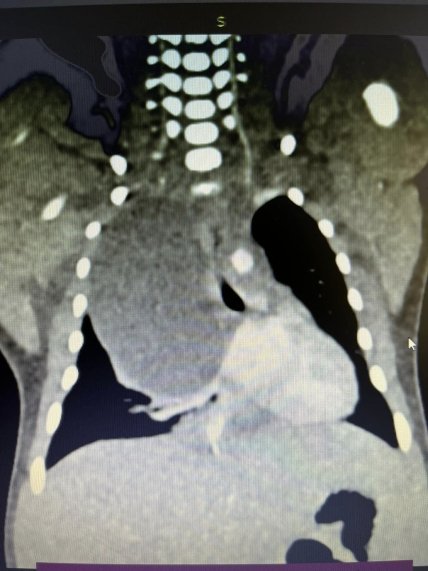

Сразу после рождения ребенок был доставлен в "Охматдет". В возрасте 5 дней медики провели обследование мальчика и наличие опухоли в правой части грудной клетки подтвердилось. Специалисты идентифицировали массивное кистовидное образование размером 36х47х62мм, которое сильно сжимало правое легкое младенца.

К счастью, опытным специалистам удалось по частям удались кисту. Была выполнена пункция, во время которой получили 30 мл муцинозного содержимого. Образование уменьшилось в размере, стало более эластичным, после чего его удалось поэтапно выделить из окружающих тканей и удалить.